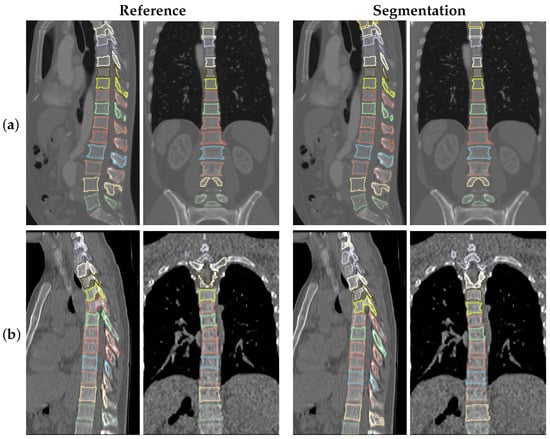

4.1. Iowa Data

4.2. VerSe2020 Data

5.1. Segmentation Performance